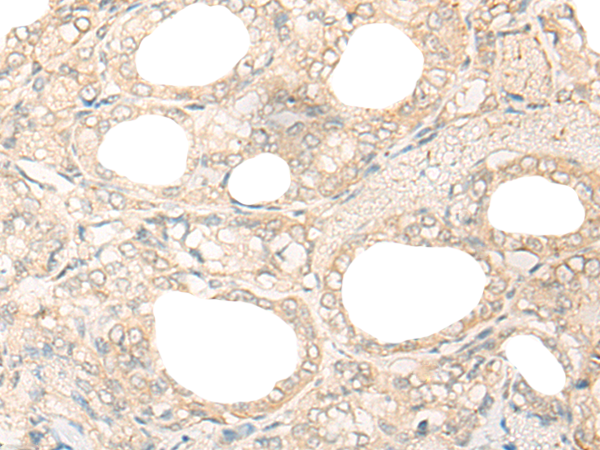

分类: 科研抗体货号: P06367别名: UHX1应用: IHC反应种属: Human